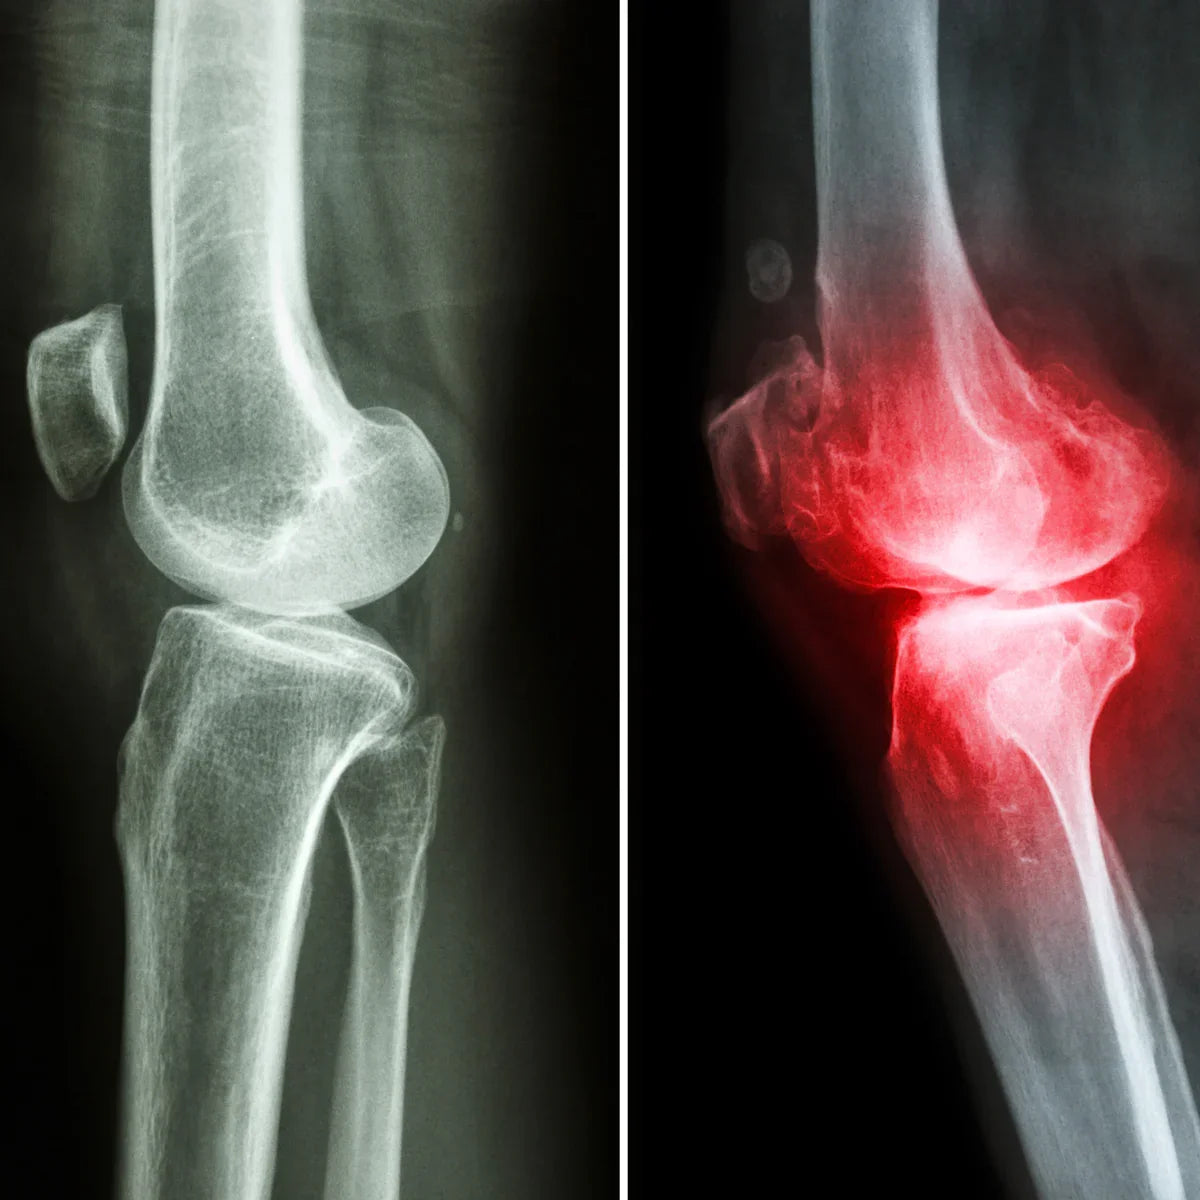

Arthro4 é um complexo com ação anti-inflamatória nas articulações e fortalecimento da cartilagem, composto por ingredientes bioativos de origem vegetal. O seu principal componente é o mexilhão de lábio verde da Nova Zelândia e inclui concentrados dos ingredientes ativos das 3 ervas mais potentes da natureza para o apoio das articulações e cartilagens: garra-do-diabo, curcuma e extrato de boswellia.

| ✓ Osteoartrite |

| ✓ Artrite reumatoide |

| ✓ Dor nas costas, dor lombar |

| ✓ Dor no joelho |

| ✓ Dor no ombro |

| ✓ Fibromialgia |

| ✓ Lupus |

| ✓ Cotovelo de tenista |

| ✓ Lombalgia |

| ✓ Asma |

O desgaste da cartilagem é causado pela degeneração da cartilagem que protege as articulações. Estudos indicam que a boswellia ajuda a prevenir estes danos nos tecidos articulares e na cartilagem. [04.]